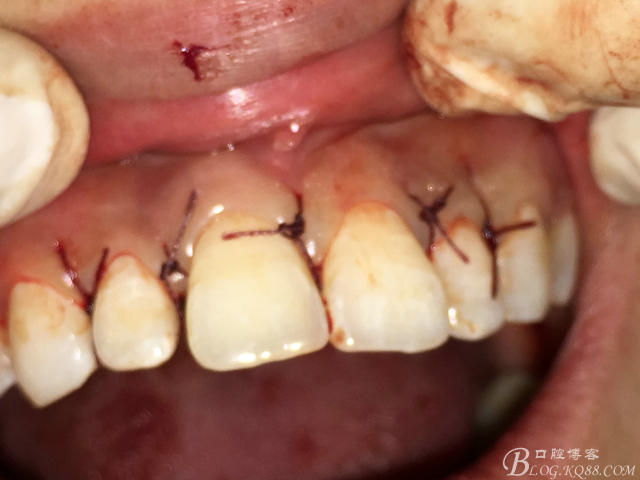

圖17.拔牙創(chuàng)口放置膠質(zhì)銀兩枚

圖18.縫合